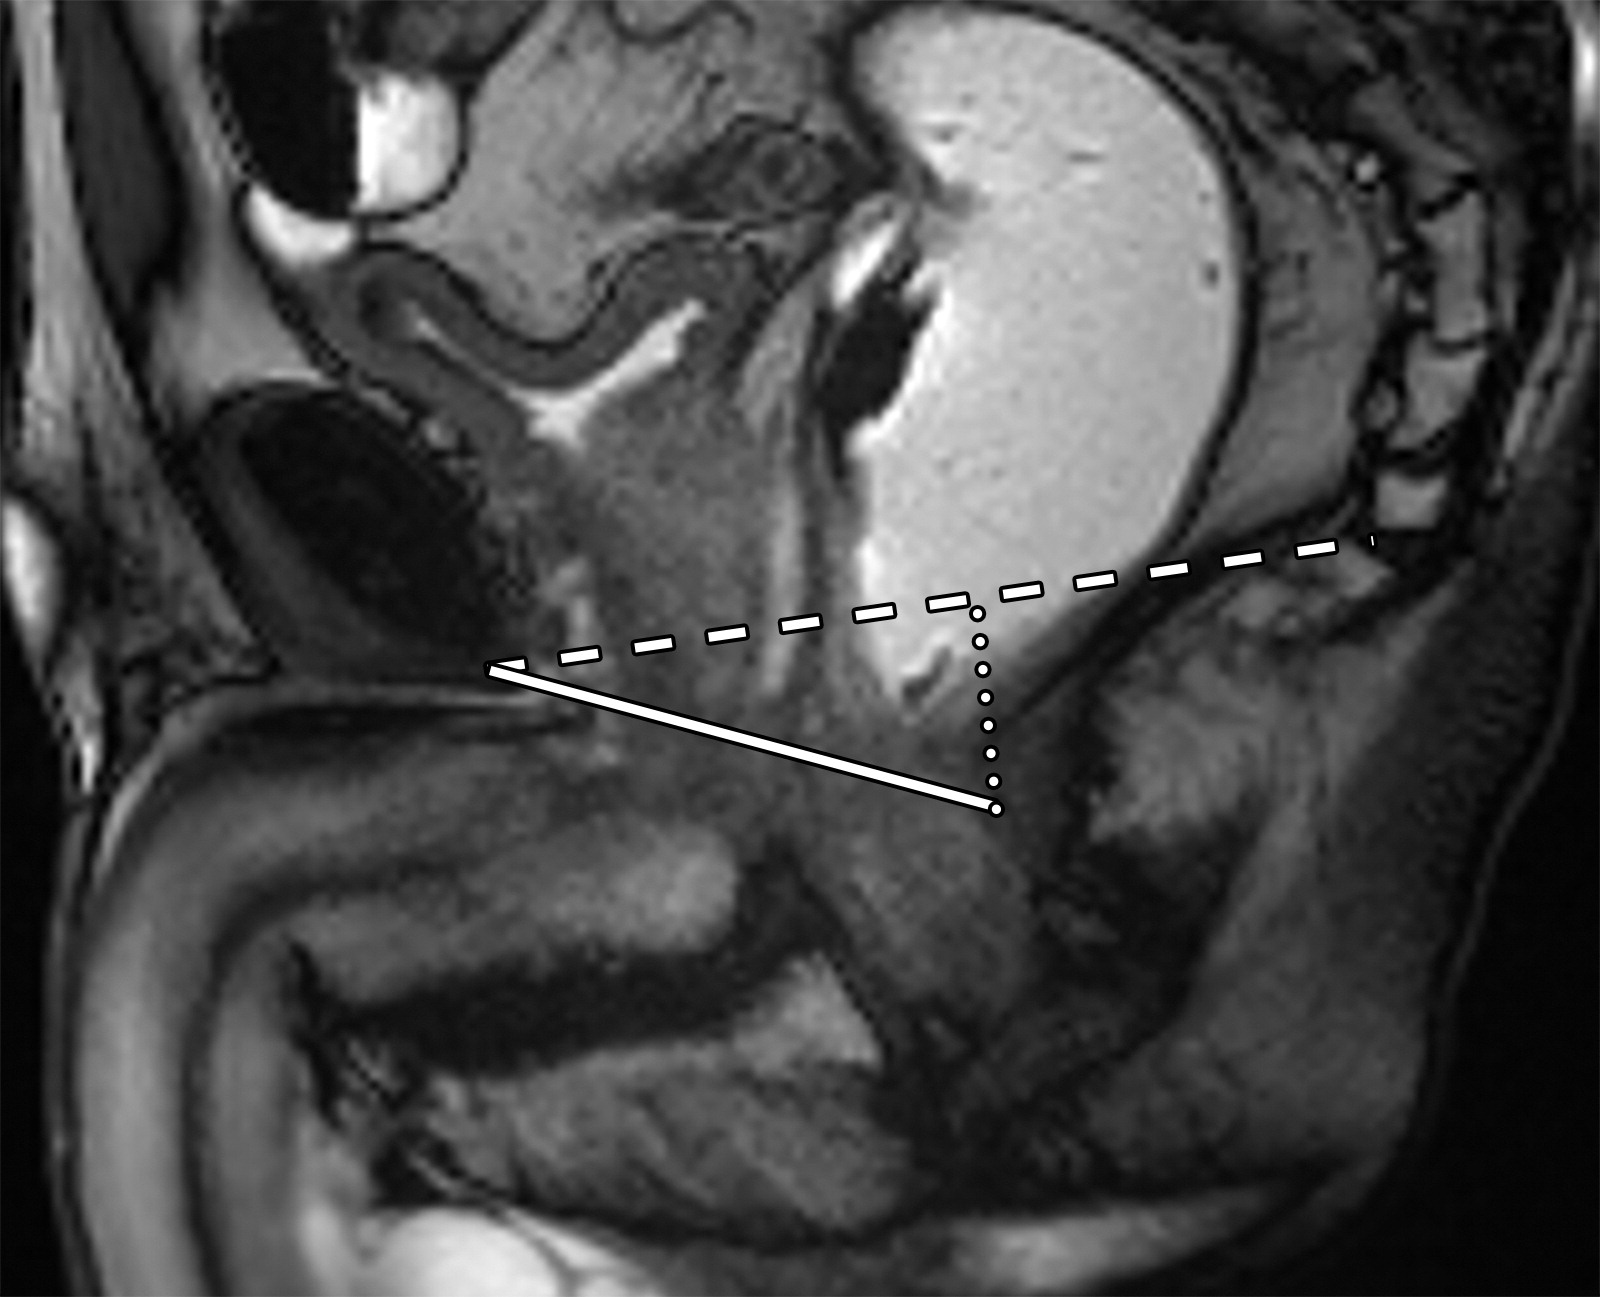

5aeb481c35f3f44c06292ac752840c01.jpeg

盆底标志线,包括PCL(白色长虚线)、H线(白色实线)、M线(白色点状虚线)。

PCL是一条从耻骨联合下缘延伸到最后尾骨关节的线。H线从耻骨联合下缘延伸至直肠后壁的线,代表提肌裂孔的前后宽度。M线是从PCL到H线的一条垂线,表示提肌裂孔下降的距离。